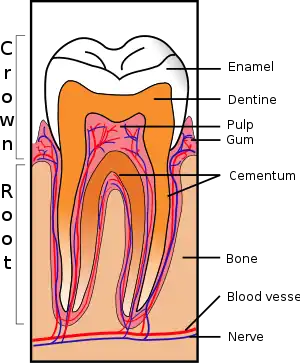

Dentin hypersensitivity (DH,[4] DHS[5]) is dental pain which is sharp in character and of short duration, arising from exposed dentin surfaces in response to stimuli, typically thermal, evaporative, tactile, osmotic, chemical or electrical; and which cannot be ascribed to any other dental disease.[5][3][6][7]

Fluid movement inside the dentinal tubules may be away from or towards the pulp. Dentine contains many thousands of microscopic tubular structures that radiate outwards from the pulp; these dentinal tubules are typically 0.5-2 micrometres in diameter. Changes in the flow of the plasma-like biological fluid present in the dentinal tubules can trigger mechanoreceptors present on nerves located at the pulpal aspect, thereby eliciting a pain response. This hydrodynamic flow can be increased by cold, (air pressure), drying, sugar, sour (dehydrating chemicals), or forces acting on to the tooth. Hot or cold food or drinks, and physical pressure are typical triggers in those individuals with teeth sensitivity. Movement of dentinal fluid away from the pulp can be caused by triggers such as cold and drying and movement towards the pulp can be caused by heat. Research has shown that triggers causing dentinal fluid to move away from the pulp elicit more of a painful response.[11]

There are two common ways in which dentine can be exposed; gingival recession and tooth wear.[9] The main cause of DH is gingival recession (receding gums) with exposure of root surfaces, loss of the cementum layer and smear layer. Receding gums can be a sign of long-term trauma from excessive or forceful toothbrushing or abrasive toothpaste (dental abrasion), or a sign of chronic periodontitis (gum disease).[10] A less common cause is acid erosion, which is the loss of hard dental tissues due to acids e.g. related to gastroesophageal reflux disease, bulimia or excessive consumption of acidic foods and drinks. Repeated exposures to a low pH cause the mineral content of the teeth on the outer layer of enamel to dissolve therefore leaving the dentine exposed and leading to hypersensitivity. Other causes include dental bleaching, smoking tobacco (which can lead to recession and therefore sensitivity) cracked teeth and abfraction or grinding of teeth. Evidence of abfraction may be shown by wedge shaped defects that are developed at the cervical region of the teeth known as abfraction lesions. There is no direct relationship between abfraction lesions and diet, periodontal disease or abrasion.[12]

Most experts on this topic state that the pain of DH is in reality a normal, physiologic response of the nerves in a healthy, non-inflamed dental pulp in the situation where the insulating layers of gingiva and cementum have been lost;[5][3] i.e., dentin hypersensitivity is not a true form of allodynia or hyperalgesia. To contradict this view, not all exposed dentin surfaces cause DH.[3] Others suggest that due to the presence of patent dentinal tubules in areas of hypersensitive dentin, there may be increased irritation to the pulp, causing a degree of reversible inflammation.[12]